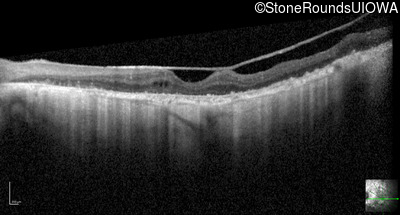

Optical Coherence Tomography - Right - <5/200

Exemplar / OCT Stack

OCT Stack